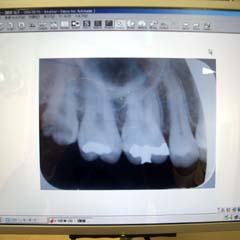

デジタルエックス線

レントゲン写真をパソコン上に取り込みます。

デジタルエックス線を使用することで、患者様の被爆量が従来の10分の1になり、さらに現像液などを使わないので廃液が発生せず、地球の環境破壊を減少させることができます。また、撮影したレントゲン写真をパソコン上の画面に映し出すことで拡大したり色の濃淡を変えられる為、わかりやすく説明できます。